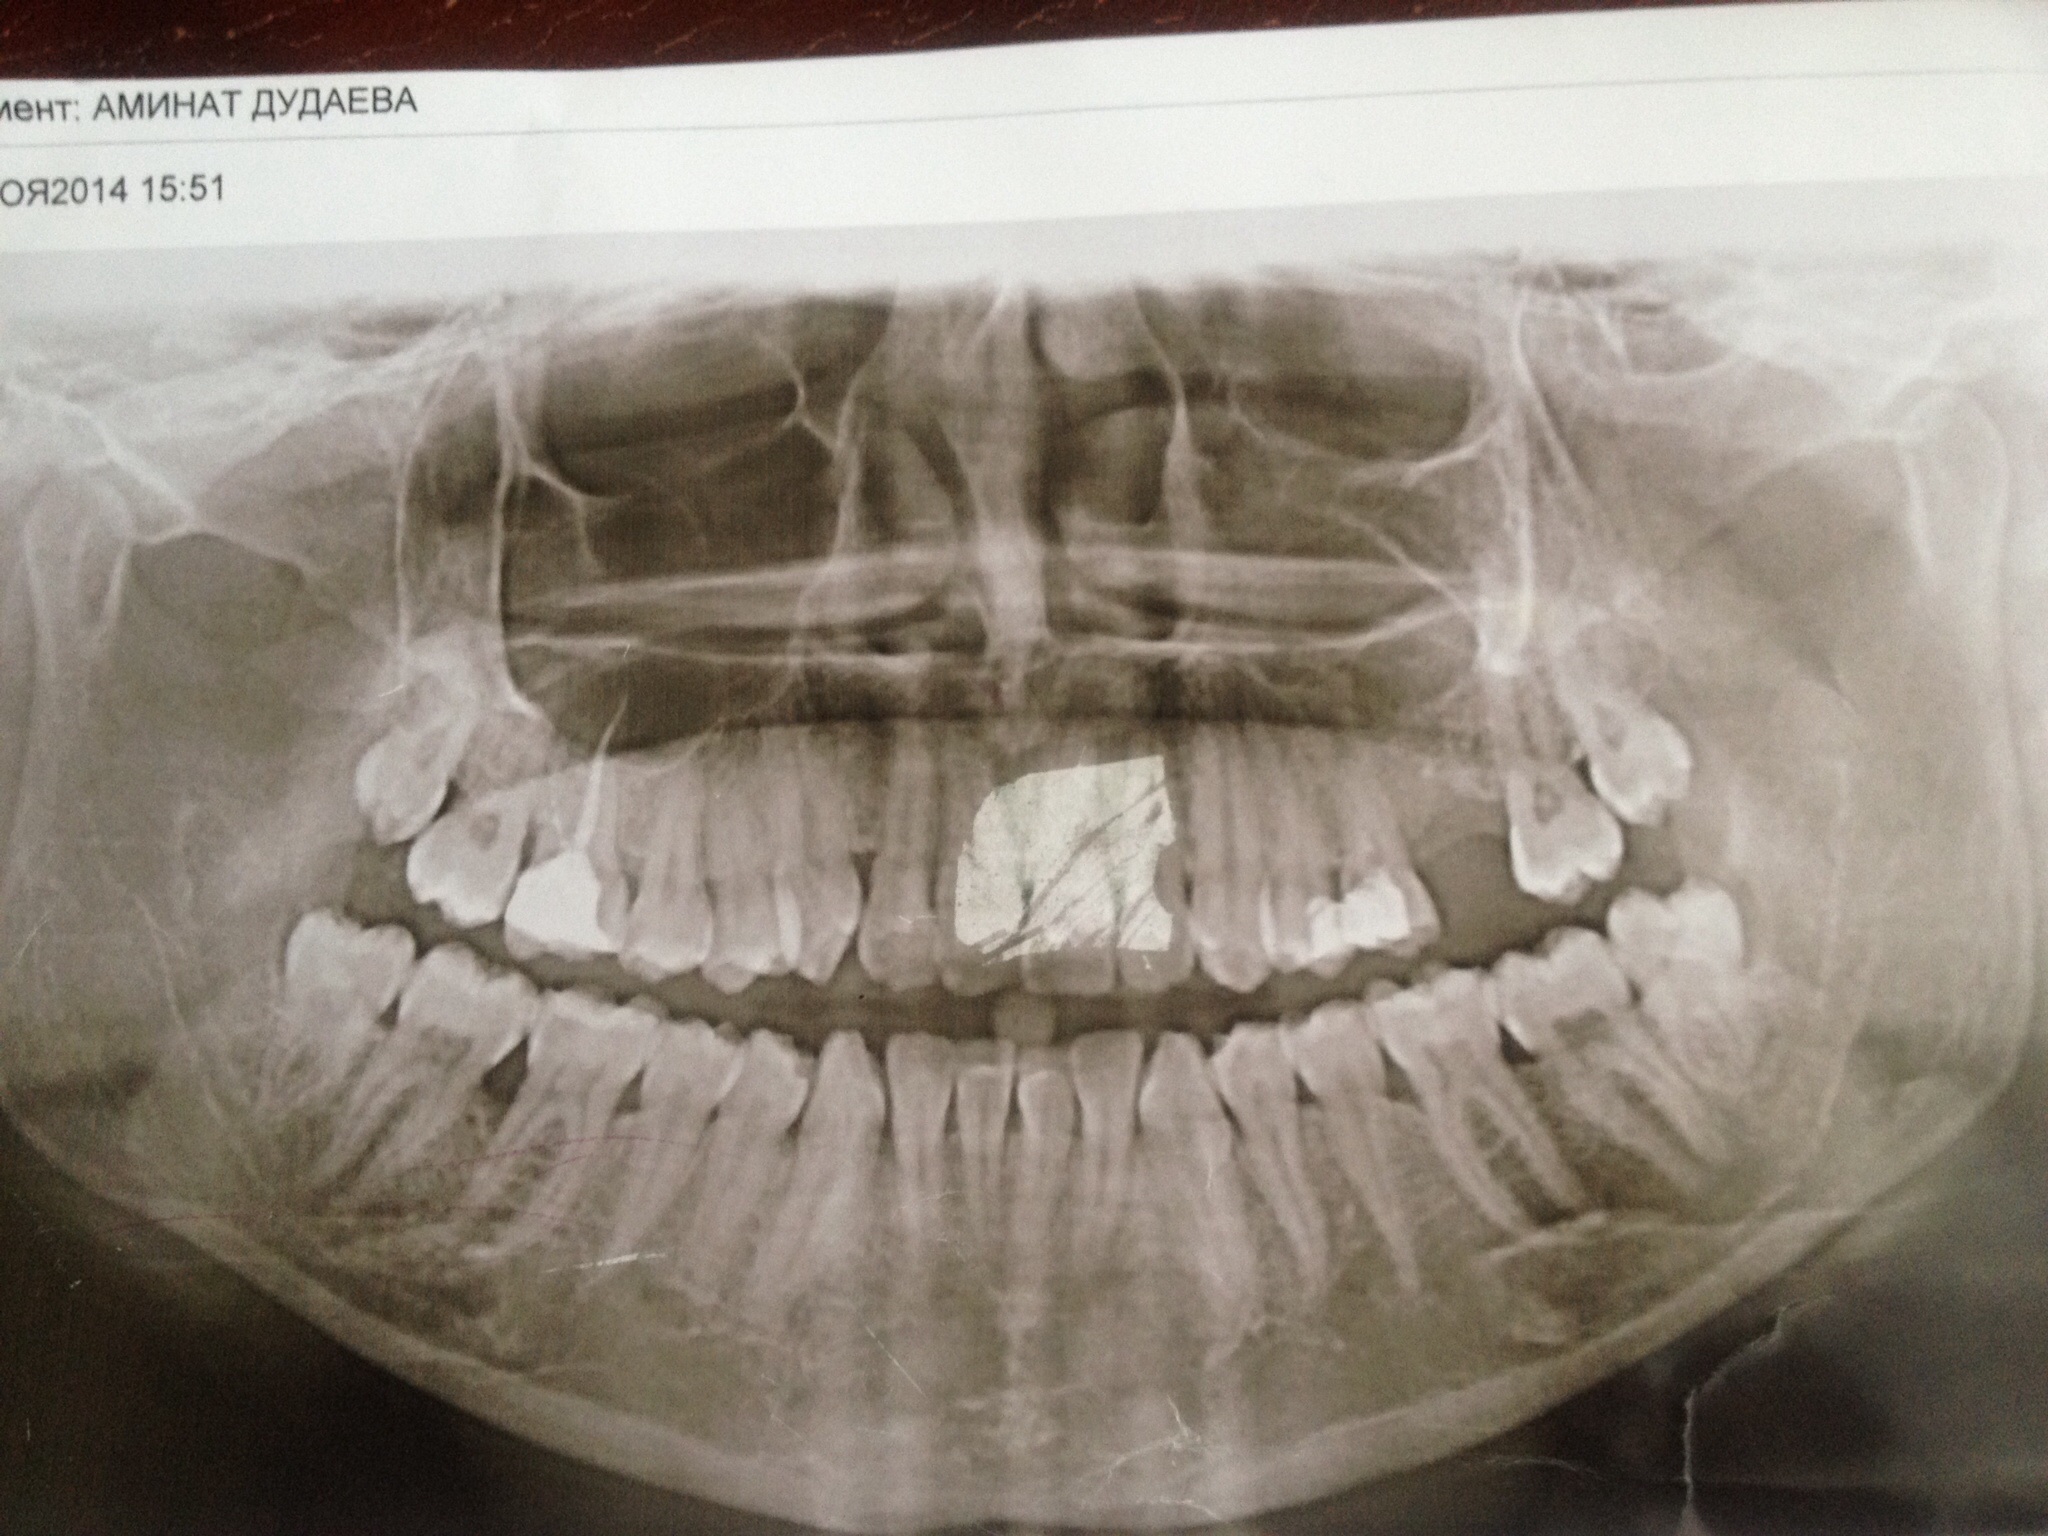

Я лечу шестой верхний зуб, мне его запломбировали вроде хорошо, но болит, и по вечерам адские боли, есть припухлость с внутренней стороны десны, боли отдают в глаз, в висок, в скулу. Врачи не могут определить, что это . Из-за этого зуба у меня в носу неприятный запах, и ноздря забита - дышать не могу! Зуб на снимке с правой стороны, левый мне удалили во время операции.

Каналы зуба пролечены некорректно, также на верхушке корней имеется воспаление (периодонтит). Ваш диагноз - обострение периодонтита, необходимо обратиться к грамотному альтернативному врачу на лечение. Кстати, на место удаленного зуба 26 пока еще можно без дополнительных манипуляций установить имплантат, объем вашей кости достаточен для процедуры имплантации.